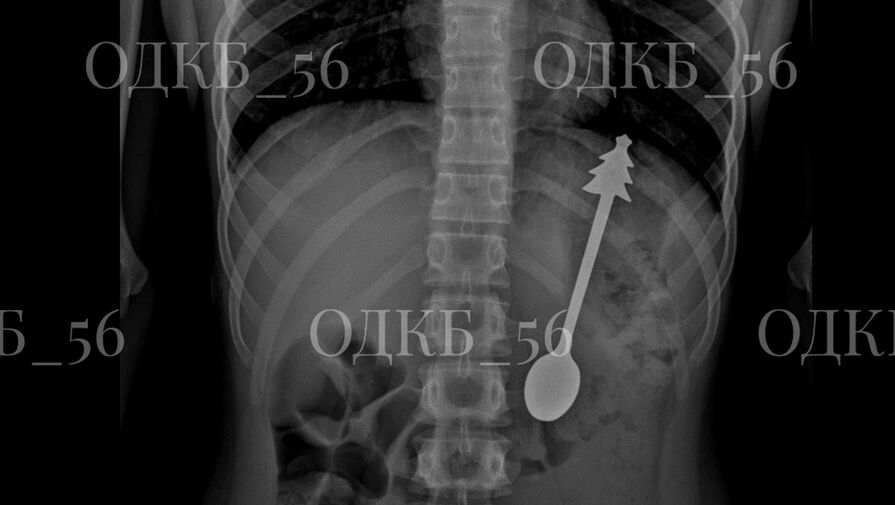

В Оренбургской области ребенок случайно проглотил 14-сантиметровую ложку

Врачи извлекли 14-сантиметровую ложку из желудка ребенка в Оренбургской области. Об этом сообщила пресс-служба регионального министерства здравоохранения на странице в социальной сети "ВКонтакте". По данным ведомства, ......